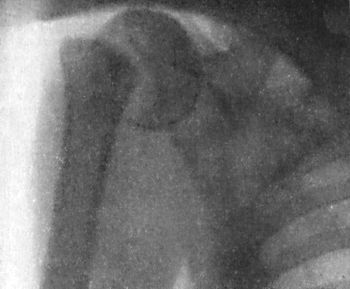

| 18. | Sub-coracoid Dislocation of Right Shoulder | 55 |

| 19. | Sub-coracoid Dislocation of Humerus | 56 |